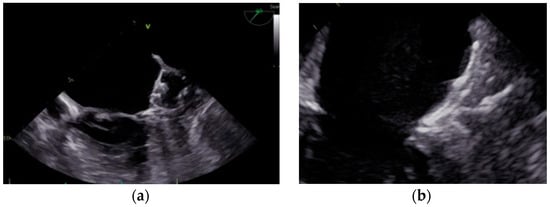

- Kanderian, A.S.; Gillinov, A.M.; Pettersson, G.B.; Blackstone, E.; Klein, A.L. Success of Surgical Left Atrial Appendage Closure: Assessment by Transesophageal Echocardiography. J. Am. Coll. Cardiol. 2008, 52, 924–929. [Google Scholar] [CrossRef] [PubMed]